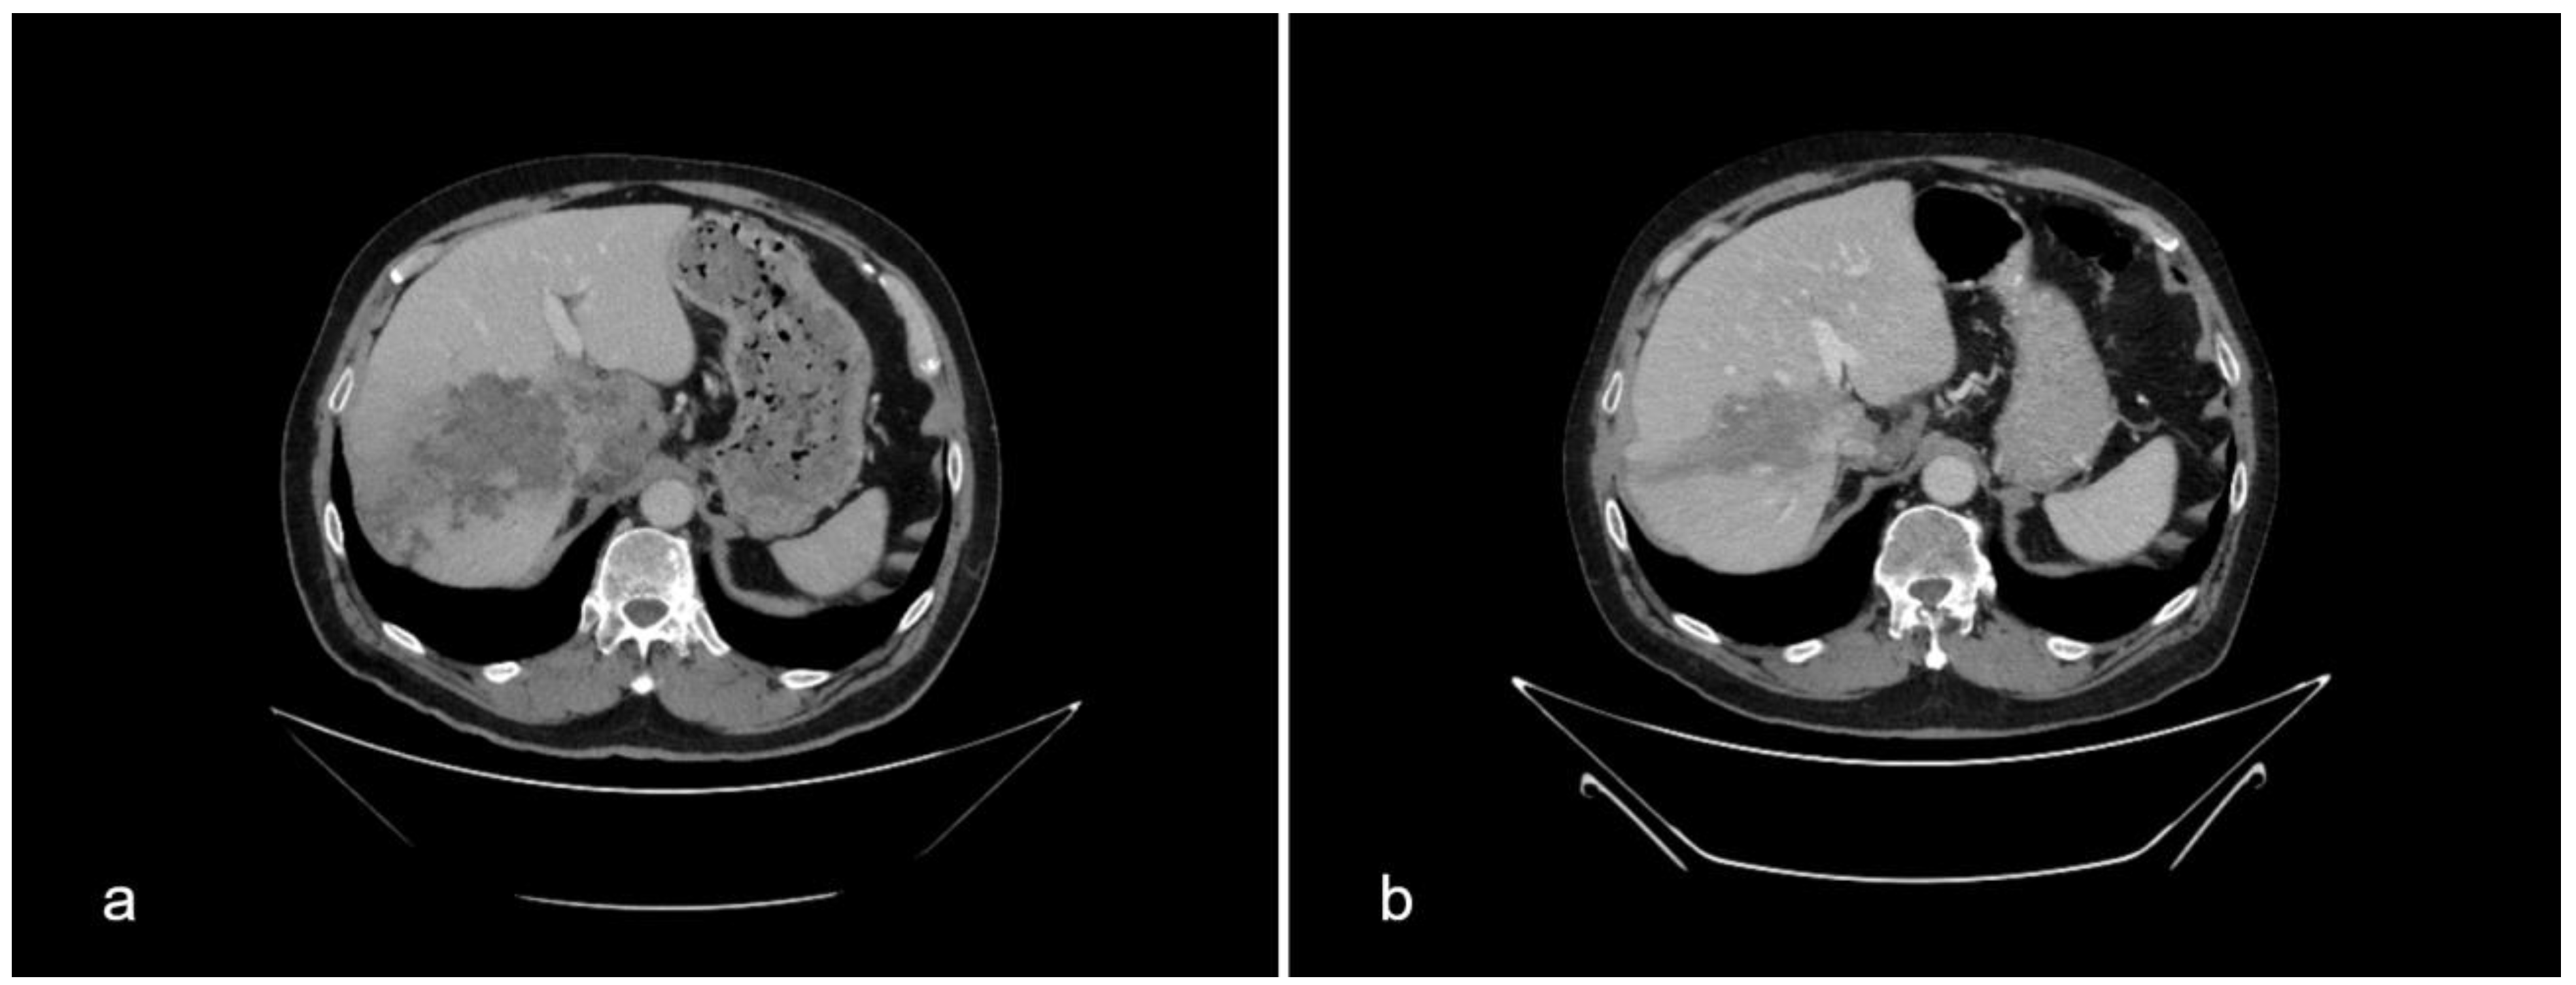

Besides IgAN, the diagnostic evaluation of kidney failure revealed a large infiltrative, poorly delineated, inhomogeneous mass of the right liver lobe (16 × 6.8 × 6.7 cm) and a necrotic nodule measuring 7 × 5 cm next to the celiac trunk (Figure 1a). The described liver lesion was first detected by abdominal ultrasound (US) and then verified by multislice computed tomography (MSCT). The radiographic appearance of the lesion was suspicious of a primary malignant liver tumor. This finding was incidental since our patient had no pain in the right upper abdominal quadrant and he was showing no signs of liver insufficiency, both clinically and according to the laboratory results. Nonetheless, chronic liver disease is often found as an accompanying condition in patients with IgAN.

The control MSCT in January 2023, following 10 weeks of antibiotic therapy and 11 months of ABZ treatment, showed regression of the lesions. The cystoid lesion of the right liver lobe was now better demarcated than initially and smaller in diameter. The necrotic nodule next to the celiac trunk decreased in size too (Figure 1b).

Figure 1. Comparison of the liver multislice computed tomography scans at the beginning of albendazole therapy in February 2022 (a) and after 11 months of treatment in January 2023 (b).